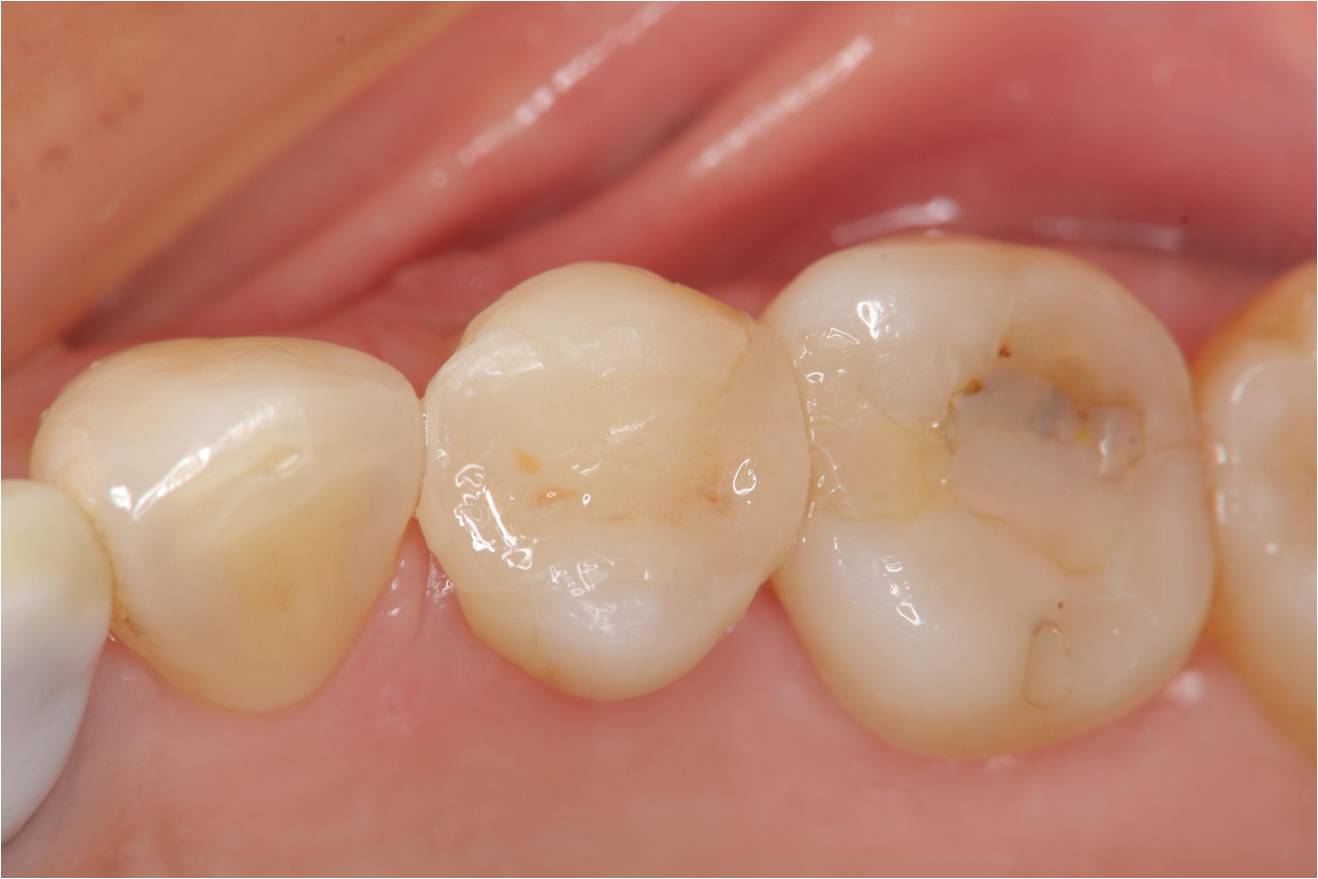

治療前,小臼齒二次蛀牙,牙崩

二次蛀牙,牙髓未受侵犯

治療後,口內照相追蹤